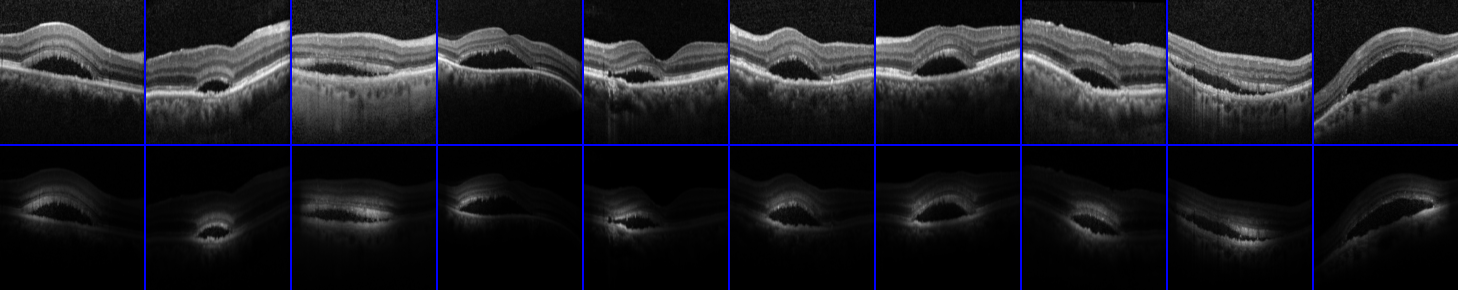

Refer to caption

A) Macular Edema

B) Normal

C) Subretinal Fluid

Figure 8: Randomly selected images and their corresponding explanations for each class from the OCT Eyes dataset.